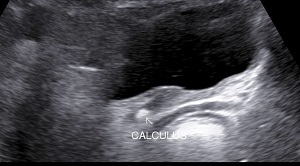

• Renal Calculi: